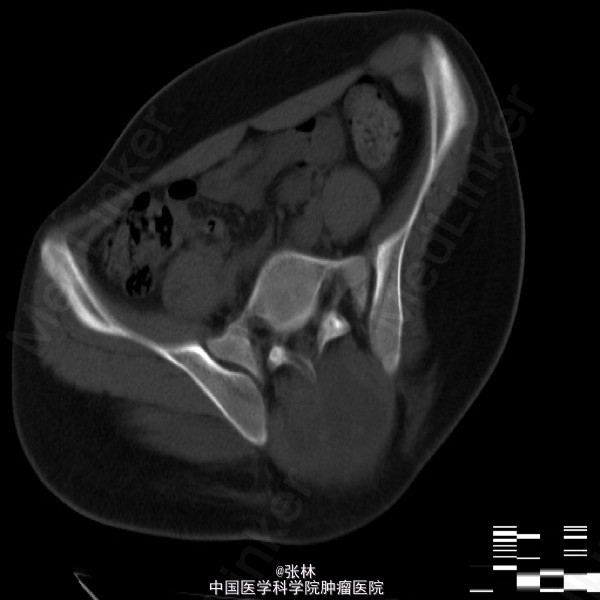

【临床病史】:患者,男,17岁,骶尾部肿物3个月,骶尾部及左腿疼痛20天,4个月前骶尾部有外伤史。【影像表现】:骶骨溶骨性骨质破坏,并软组织肿块。 【影像诊断】:神经源肿瘤? 脊索瘤?骨髓瘤? 【最后诊断】:术后病理结果:动脉瘤样骨囊肿。 【讨论】:动脉瘤样骨囊肿(ABC)为一充满血液的肿瘤样病变,因其外形似动脉瘤样的囊状膨出而得名。好发长骨干骺端和脊椎,年龄10-20岁。病因不明,一般以为外伤是重要诱因,外伤、静脉血栓、动静脉瘘、血管瘤、骨膜下囊肿或其他疾病因素导致局部血液动力的障碍、静脉压持续升高,患骨血管床扩张,压迫骨质吸收并寄发感染反应性修复而形成囊肿。特征性影像表现液-液平面;而脊索瘤应该有散在钙化;动脉瘤样骨囊肿的吸收性骨质破坏是此病例鉴别诊断的关键!